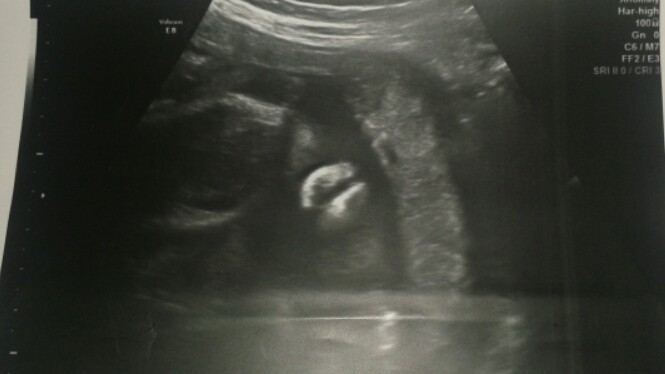

Matko boska to moze to obojniak [emoji23][emoji23][emoji23][emoji23][emoji23][emoji23][emoji23][emoji23]

Ale mnie dziecie I ci lekarze zrobili w balona.

Chyba dowiem sie na stole dopiero kto tam siedzi [emoji23][emoji23][emoji23][emoji23]

@joshi pindol synka z 6 m-ca. Wyglàda podobnie :) u mnie przy każdym usg zauważajà, że Kierownik ma konkretny sprzèt. Coś mi siè wydaje, że Lenka może być Leo ;)

Co mnie tylko zastanawia gdzie on ma jajka !!!! Bo u ciebie sa bardzo widoczne mimo iz sprzet konkretny.

U mnie tych jajek nie widac a sam pindolek.